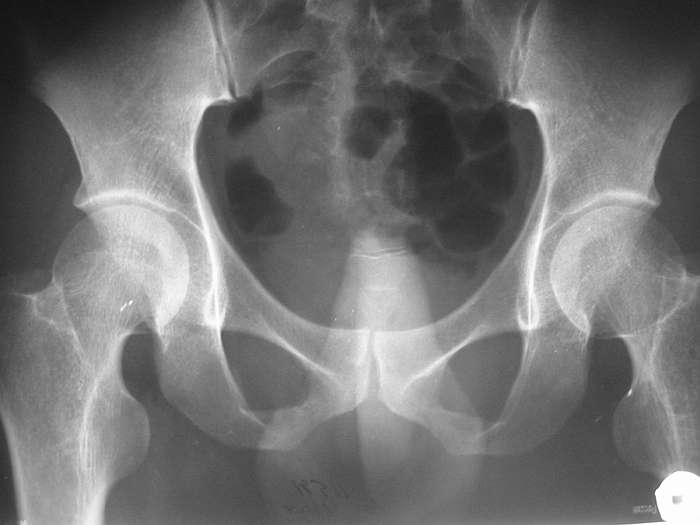

ЗЫ: В приложении снимок таза.

СА> P.S. хотелось бы увидеть снимок таза

Сегодня забегался и забыл про снимок, sorry. Завтра выложу.